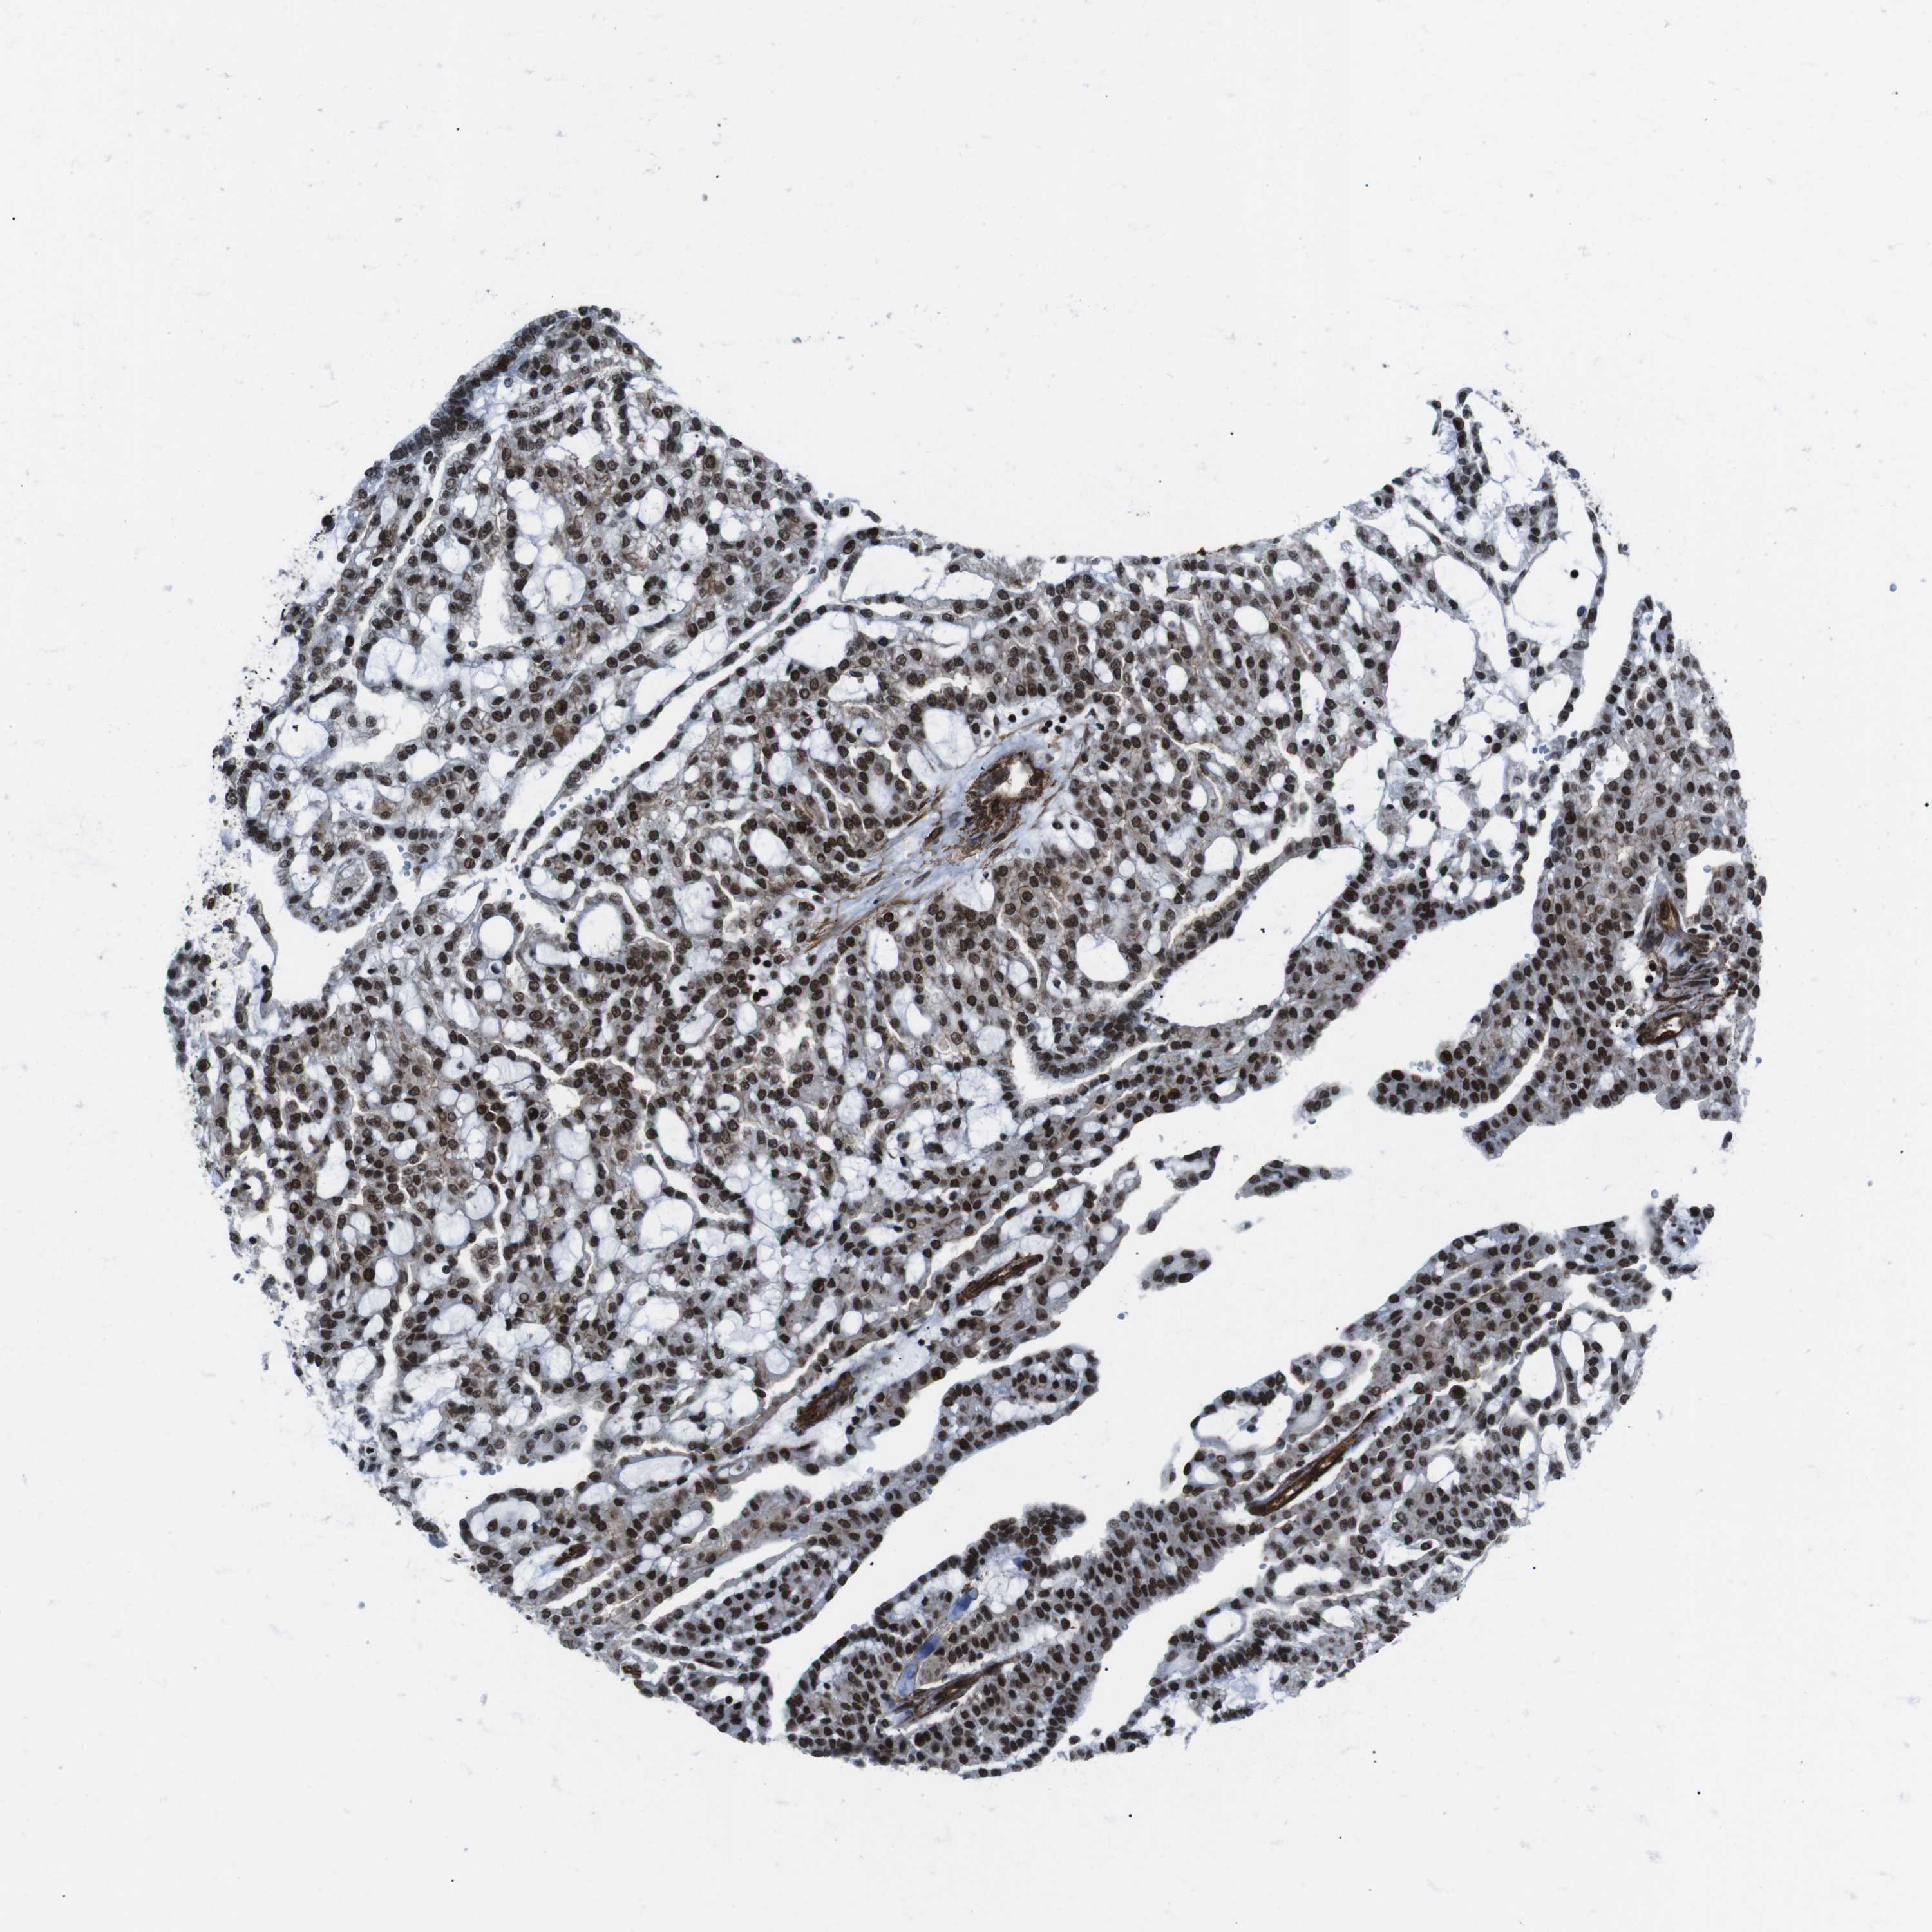

KIDNEY RENAL CLEAR CELL CARCINOMA (VALIDATION) - Interactive survival scatter ploti

The Survival Scatter plot shows the clinical status (i.e. dead or alive) for all individuals in the patient cohort, based on the same data that underlies the corresponding Kaplan-Meier plots. Patients that are alive at last time for follow-up are shown in blue and patients who have died during the study are shown in red.

The x-axis shows the expression levels (FPKM) of the investigated gene in the tumor tissue at the time of diagnosis. The y-axis shows the follow-up time after diagnosis (years). Both axes are complimented with kernel density curves demonstrating the data density over the axes. The top density plot shows the expression levels (FPKM) distribution among dead (red) and alive patients (blue). The right density plot shows the data density of the survived years of dead patients with high and low expression levels respectively, stratified using the cutoff indicated by the vertical dashed line through the Survival Scatter plot. This cutoff is automatically defined based on the FPKM cutoff that minimizes the p-score. The cutoff can be changed by dragging the vertical line or by entering a cutoff value in the square labeled "Current cut-off".

Under the Survival Scatter plot the p-score landscape (black curve; left axis) is shown together with dead median separation (red curve; right axis). Dead median separation is the difference in median mRNA expression between patients who have died with high and low expression, respectively. It is calculated as follows: median FPKM expression of dead patients with high expression - median FPKM expression of dead patients with low expression. This is intended to aid the user in visually exploring custom cutoffs and the associated p-scores and dead median separation.

Individual patient data is displayed and can be filtered by clicking on one or more of the category buttons on the top of the page. Categories describing expression level and patient information include: high, low, alive, dead, female, male and tumor stages. The scale of the x-axis can be toggled between linear and log-scale by clicking on the "x log" button. Mouse-over function shows TCGA ID, patient information and mRNA expression (FPKM) for each patient.

& Survival analysisi

Kaplan-Meier plots summarize results from analysis of correlation between mRNA expression level and patient survival. Patients were divided based on level of expression into one of the two groups "low" (under cut off) or "high" (over cut off). X-axis shows time for survival (years) and y-axis shows the probability of survival, where 1.0 corresponds to 100 percent.

HNRNPU is not prognostic in Kidney Renal Clear Cell Carcinoma (validation)

Best expression cut offi

Based on the FPKM value of each gene, patients were classified into two groups and association between prognosis (survival) and gene expression (FPKM) was examined. The best expression cut-off refers the FPKM value that yields maximal difference with regard to survival between the two groups at the lowest log-rank P-value. Best expression cut-off was selected based on survival analysis .

When clicking on this number, the vertical dashed line indicating cut-off, the interactive survival plot, and the Kaplan-Meier curve will be adjusted to show results based on the best expression cut-off.

: 133.42

TCGA RNA samplesi

RNA-seq data is reported as average FPKM (number Fragments Per Kilobase of exon per Million reads), generated by the The Cancer Genome Atlas (TCGA) .

Normal distribution across the dataset is visualized with box plots, shown as median and 25th and 75th percentiles. Points are displayed as outliers if they are above or below 1.5 times the interquartile range. FPKM values of the individual samples are presented next to the box plot.

Average pTPM 159.5

Number of samples 100